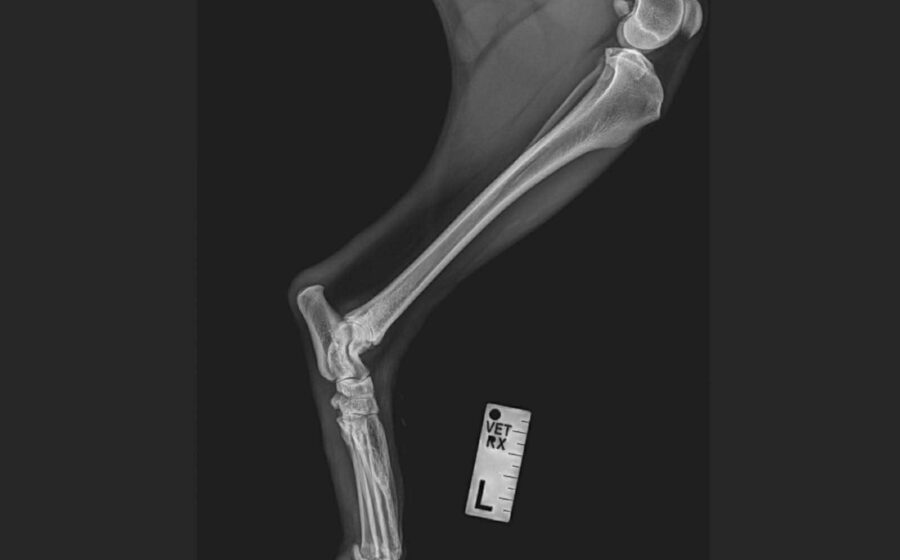

Inura ist eine wunderschöne junge Husky-Hündin, die trotz schwerer Vergangenheit eine beeindruckende Stärke und Sanftmut in sich trägt. Sie wurde an Bahngleisen gefunden – verletzt, verängstigt und ganz allein. Ein Zug hatte ihr mehrere Zehen am Hinterbein abgetrennt. Dank eines aufmerksamen Mannes kam sie sofort in tierärztliche Behandlung und konnte gerettet werden. Ihre Pfote ist inzwischen gut verheilt, doch die fehlenden Zehen werden für immer bleiben.

Aktuell humpelt sie und belastet das Bein nur begrenzt. Unsere Tierärztin geht davon aus, dass Inura ihr Leben lang humpeln wird. Das ist nicht dramatisch für sie, aber es bedeutet, dass sie besondere Unterstützung verdient. Eine Orthese – also eine speziell angepasste Stütze – könnte ihr künftig hervorragend helfen. Sie würde den Druck auf die empfindliche Pfote reduzieren, den Kontakt zum Boden abfedern und ihr das Laufen erleichtern, besonders auf härteren Untergründen. Mit etwas Muskelaufbau, sicheren Böden und dieser zusätzlichen Unterstützung kann Inura sich gut und stabil durchs Leben bewegen.